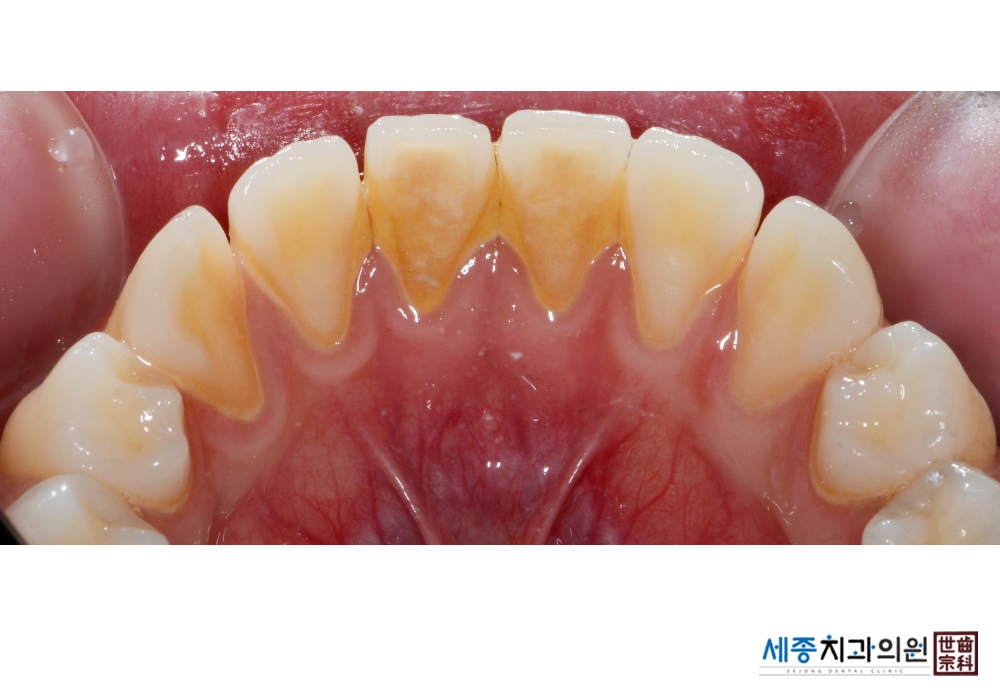

[스케일링] 치주질환 예방 스케일링

치료전 : 2020-02-14

치료후 : 2020-02-14

가글마취&저주파 스켈러를 사용한 스케일링